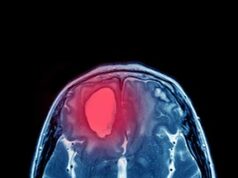

Les tumeurs de l’oropharynx doivent être biopsiées. Pour certaines tumeurs accessibles en clinique, des biopsies peuvent être réalisées sous anesthésie locale. Pour les autres tumeurs, les biopsies sont souvent réalisées au bloc opératoire pendant que le patient dort. Cela permet une évaluation approfondie de l’étendue de la tumeur et fournit des informations pour planifier le traitement en plus des informations de diagnostic. Une biopsie par aspiration à l’aiguille fine, une procédure qui place une petite aiguille dans la masse du cou pour extraire les cellules, est réalisée sous anesthésie locale dans une clinique. Cela permet à un pathologiste d’évaluer les cellules au microscope pour déterminer si la masse du cou est cancéreuse et si elle est liée au VPH. Un bilan complet implique l’imagerie, qui peut inclure une IRM, une tomodensitométrie ou une tomographie par émission de positrons (TEP).